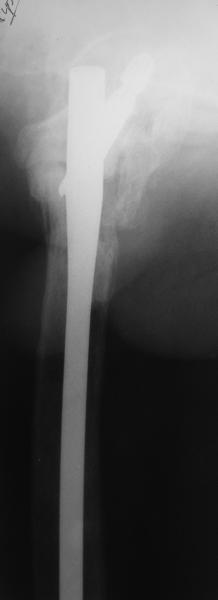

В приложении пример пациента, близкого по картине к тому, что представил Виктор (варус и смещение периферического отломка на поперечник кзади). Сделали как раз то, что Виктор исходно намеревался - аппаратная коррекция и затем гамма.

По опыту подобных случаев, аппарат лучше на бедро, без таза пока. В проксимальный фрагмент 3 стержня по оси шейки. Дистальный - хватит 1 стержня или 2 спиц в дистальном метафизе и 1 стержня вверху. Если планируете гвоздь, надо с гиперкоррекцией восстановить длину и ось, т.е. вальгизировать проксимальный отдел. При наложении аппарата сделать остеоклазию, добиться уверенной подвижности. Регенерат не нужен, тяните на пределе переносимости пациентом - хоть 2 см/сут. Обычно меньше.

Второй этап - на следующий день после окончания коррекции.

Если все получилось, т.е. закрыто сопоставить с гиперкоррекцией, накладываете дистрактор таз-бедро или используете тракционный стол, и гвоздь можно делать закрыто. Пластика то есть не нужна. Если клинковая пластина - может получиться как при меежвертельной остеотомии, боковая компрессия by mismatch. Тогда тоже пластика не нужна. Если не получатся, можно и сделать.